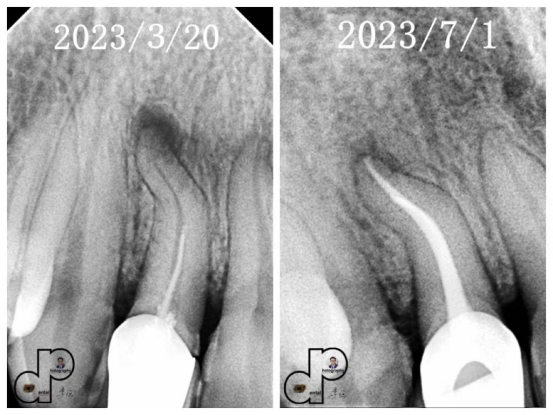

年轻恒牙粗大根管根尖周炎的根尖诱导成型术 粗大根管治疗的根尖屏障术。 血运重建术的适应症、特点及操作步骤。 实操:离体牙上实操活髓切断术及根尖屏障的操作步骤。

活髓切断术的适应症 牙外伤的分类及治疗概况 Andreasen前牙折裂的分类 牙根未发育完成的年轻恒牙的特点 损伤牙髓修复和活髓保存的生物学基础 活髓保存术中牙髓状态的评估 活髓保存的直接盖髓材料的选择 牙髓切断术成功的关键及操作步骤 深龋充填的间接盖髓与露髓的直接盖髓的材料选择及操作步骤